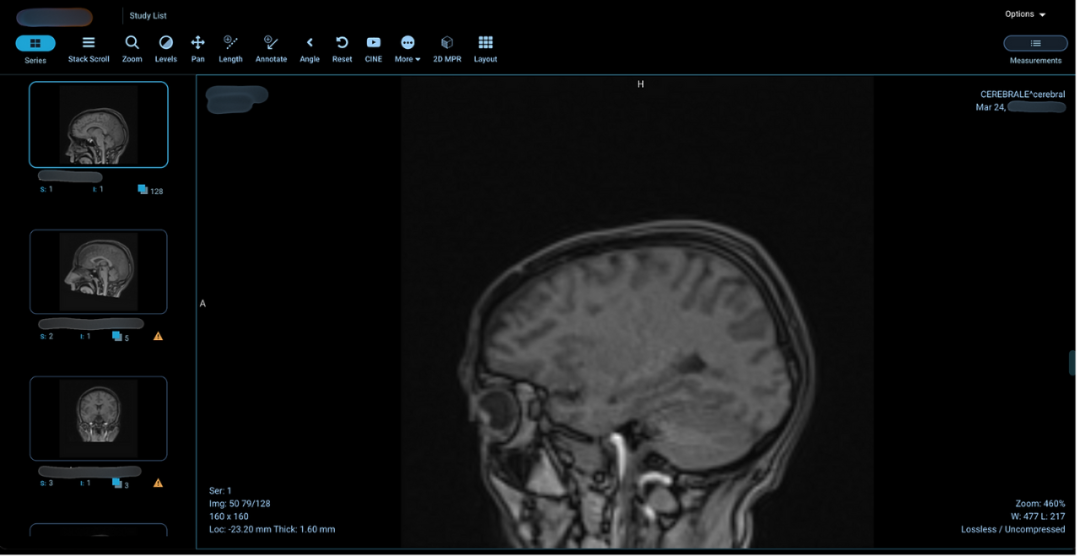

图:暴露在公网上的含受保护健康信息(PHI)的颅骨X光图像

图:包含患者详细信息的胸部、肺部及腿部磁共振扫描图像

泄露的数据样本包括大脑扫描图像和X光片,这些图像通常与受保护健康信息及患者个人身份信息共同存储,可能对患者的保密权和隐私造成双重侵犯。

由于这些扫描仪未进行安全配置,研究人员发现了一些包含患者姓名和扫描日期的大脑图像。采用类似方法,他们还获取了其他多种类型的医疗图像,包括验光师的眼科检查图像、牙科X光、血液检查结果,甚至用于肺癌患者诊疗的详细肺部磁共振图像。被曝光的医疗文件数量之大,令人震惊。